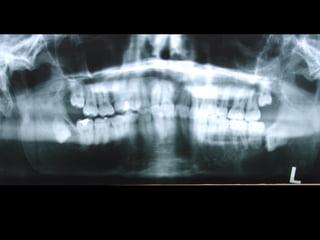

Diagnóstico por Imágenes •Rx Extraorales: Teleradiografías y Ortopantomografías • Rx intraorales: Oclusales y Rx. Periapicales. • Fundamentalmente Tomografías

Rx Intraoral: TécnicaDe Cono Largo • Altura de hueso disponible • Relación con estructuras anatómicas • Amplitud • Relación con piezas vecinas • Presencia de patologías y-o cuerpos extraños • Traveculado óseo

Rx Panorámica

Distorciónes en Diferentes Sectores de la Panorámica

En Sentido Vertical

30 %30 %

Sector

Anterior

10 %10 %

Posterior

Distorciónes de la Panorámica

En Sentido Horizontal

Hasta un 70 %Hasta un 70 %